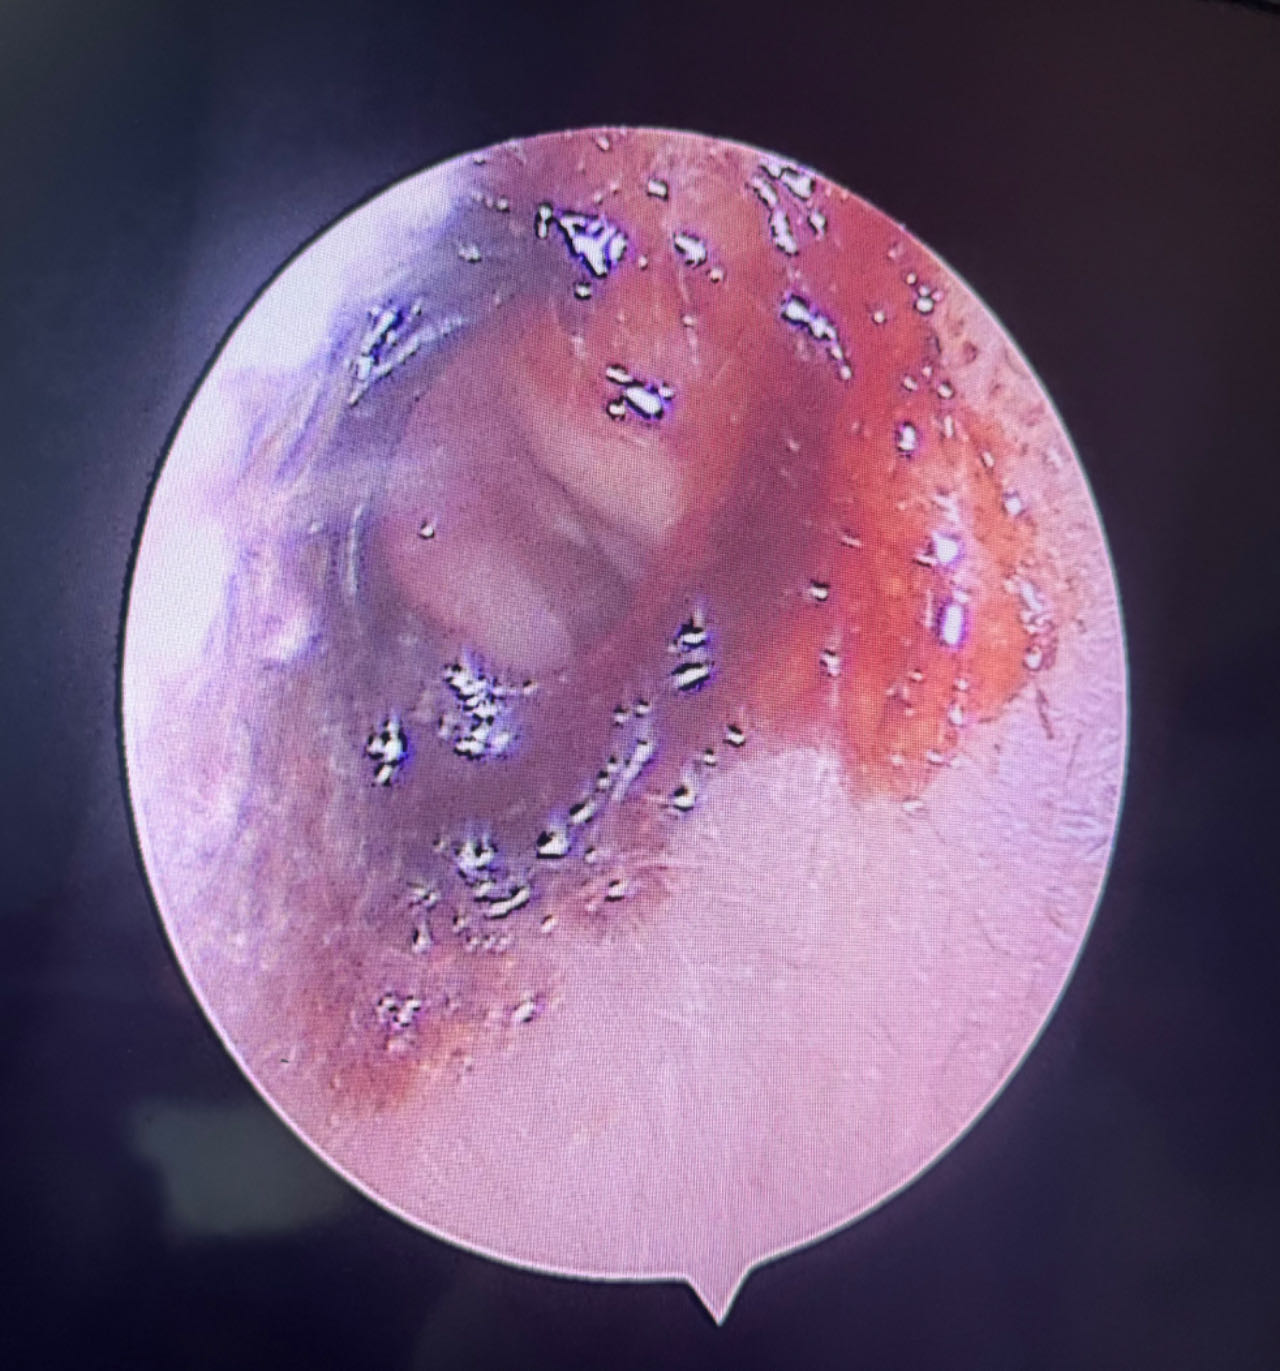

检查显示彤彤右耳道轻微红肿,左耳道内可见大量血液脓性分泌物。于是,对彤彤进行了左耳道清洗,清洗后显示外耳道壁可见多处脓肿、局部破溃、鼓膜完整。